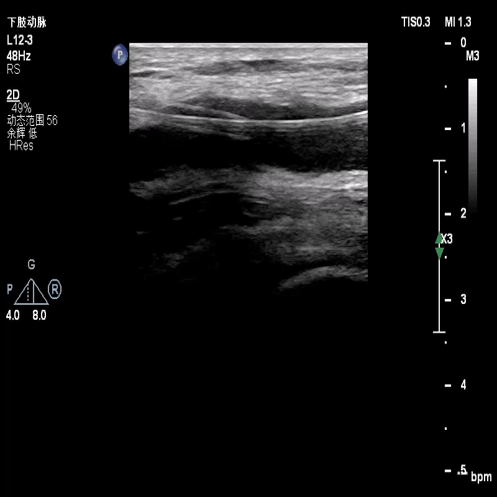

术前超声评估:提示腘动脉血栓。

图:胫腓干血栓及直径

胫后及腓动脉起始处彩色血流图